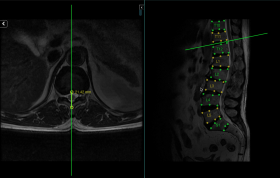

Synapsica Spindle

Spindle is our AI reporting assistant for MRI Spine. It generates preliminary reports with necessary spinal measurements and characterisation of degenerative changes.